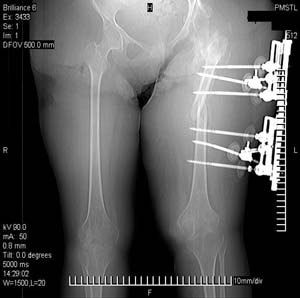

Пациентка 17 лет. В 5-летнем возрасте получила кататравму - осложнённый перелом позвоночника с повреждением спинного мозга в грудном отделе, нижняя параплегия с нарушением функции тазовых органов. Поступила к нам в отделение в сентябре 2007 по поводу патологического перелома левого бедра на фоне хронического остеомиелита бедра. Лечение стержневым аппаратом АВФ, достигнута консолидация. За время лечения развились массивные пролежни крестца и правого бедра с переходом в остеомиелит в/3 правого бедра, сепсис. Выполнено вскрытие гнойника, некрэктомия. Рана велась открыто. В дальнейшем - повторные некрэктомии, дермотензия.

Хотелось бы увидеть рану с разных ракурсов и рентгенограммы таза и бедра. Тогда можно создать представление о площади и глубине раны.

>Можно наложить простейший аппарат таз-бедро и подвесить больного

Такая мысль тоже приходила. Не решились, так как:1.Выраженный остеопороз костей таза и бедра, больная тучная - высок риск того, что стержни не выдержат. 2.Сейчас больная передвигается в инвалидном кресле - хоть какая-никакая, а динамизация. Если лишить её этой возможности - застойная пневмония со всеми вытекающими...